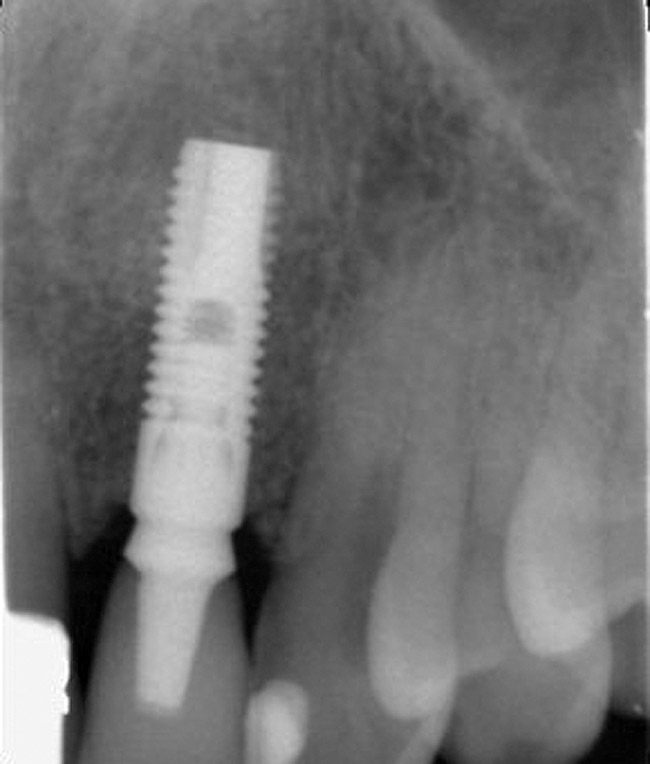

Figure 4  Characterization of the interproximal bone and tooth contacts: A periapical radiograph assists in measuring the distance from bone crest to the adjacent tooth contact points for missing tooth No. 8. The mesial bone crest to the adjacent tooth contact distance is < 5 mm, while the distal bone crest to adjacent tooth contact distance is > 6 mm (Fig 4). One-year following implant placement, conservation of these dimensions is revealed (Fig 5). The clinical photograph (Fig 6) of the lateral incisor adjacent to tooth No. 8 implant crown demonstrates that the absence of distal interproximal (papilla) fill related to the observed bone crest to contact distance exceeds 6 mm.

Figure 5  Characterization of the interproximal bone and tooth contacts: A periapical radiograph assists in measuring the distance from bone crest to the adjacent tooth contact points for missing tooth No. 8. The mesial bone crest to the adjacent tooth contact distance is < 5 mm, while the distal bone crest to adjacent tooth contact distance is > 6 mm (Fig 4). One-year following implant placement, conservation of these dimensions is revealed (Fig 5). The clinical photograph (Fig 6) of the lateral incisor adjacent to tooth No. 8 implant crown demonstrates that the absence of distal interproximal (papilla) fill related to the observed bone crest to contact distance exceeds 6 mm.

Figure 6  Characterization of the interproximal bone and tooth contacts: A periapical radiograph assists in measuring the distance from bone crest to the adjacent tooth contact points for missing tooth No. 8. The mesial bone crest to the adjacent tooth contact distance is < 5 mm, while the distal bone crest to adjacent tooth contact distance is > 6 mm (Fig 4). One-year following implant placement, conservation of these dimensions is revealed (Fig 5). The clinical photograph (Fig 6) of the lateral incisor adjacent to tooth No. 8 implant crown demonstrates that the absence of distal interproximal (papilla) fill related to the observed bone crest to contact distance exceeds 6 mm.